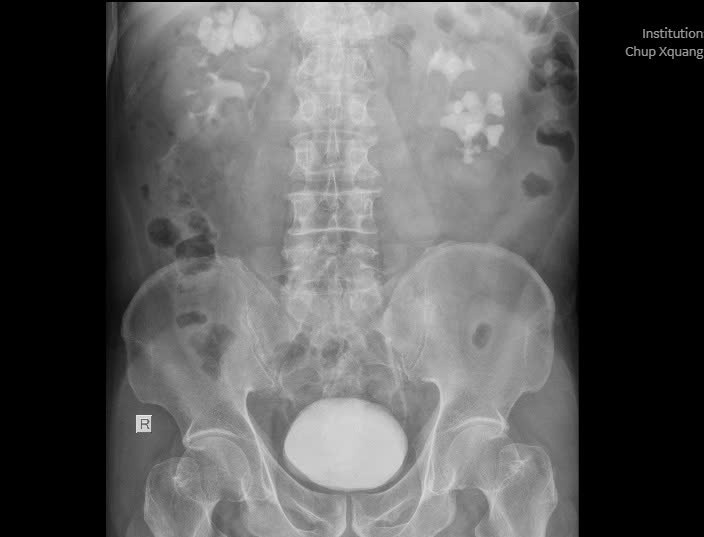

Kết quả thăm khám và xét nghiệm cho thấy bệnh nhân có sỏi ở cả hai bên thận, trong đó thận phải chứa một khối sỏi san hô kích thước lên đến 35x30x22mm, kèm nhiều viên nhỏ khác.

Sỏi san hô khổng lồ ở cả 2 bên thận trên phim chụp - Ảnh BVCC